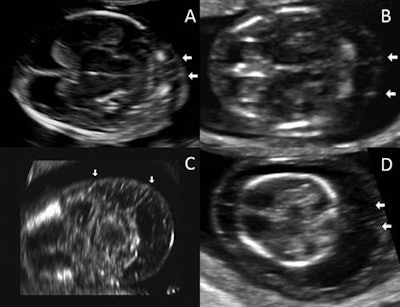

Ultrasound images of nuchal septations in a transverse plane. Image A has a nuchal translucency of 2.3 mm, while image B has a nuchal translucency of 4 mm. Image C has a nuchal translucency of 5.2 mm and image D has a nuchal translucency of 8 mm. All images courtesy of the Journal of Ultrasound in Medicine.The prevalence of chromosomal abnormalities was significantly higher than in fetuses with normal nuchal translucency (p < 0.001), as well as in those with nuchal translucency above the 95th percentile but without septations (p < 0.001), the researchers found. What's more, after controlling for nuchal translucency measurements and other confounding variables, evidence of septations offered an odds ratio of 40 (95% confidence interval: 9.1-174) for chromosomal abnormalities. That was nearly twice the odds ratio of 20.9 (95% confidence interval: 7.2-60.6) for the presence of nuchal translucency alone of at least the 95th percentile.